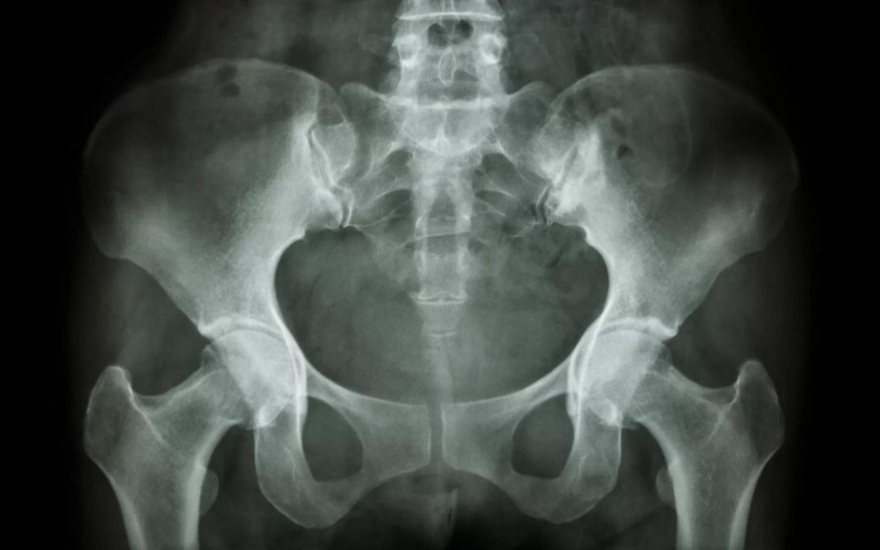

Chụp X-quang và CT: Ở giai đoạn sớm, chụp X-quang chưa phát hiện được tổn thương khớp cùng chậu. Tuy nhiên, khi bệnh tiến triển nặng, chụp X-quang và CT có thể cho thấy tình trạng khe khớp cùng chậu rộng, xơ cứng trên bề mặt khớp, bào mòn khớp, dính một phần khớp cùng chậu... Giai đoạn 4: dính khớp cùng chậu hoàn toàn.

Chụp cộng hưởng từ (MRI): Ngoài các hình ảnh có thể thấy trên X-quang, CT, chụp MRI còn cho thấy mức độ tổn thương viêm khớp cùng chậu, cơ, dây chằng, phần mềm quanh khớp, các vết nứt gãy nhỏ tại vị trí khớp. Chụp cộng hưởng từ có thể giúp chẩn đoán viêm khớp cùng chậu từ giai đoạn khởi phát, trong khi X-quang và CT không phát hiện được.

Hình ảnh viêm khớp cùng chậu trên phim chụp X-quang.